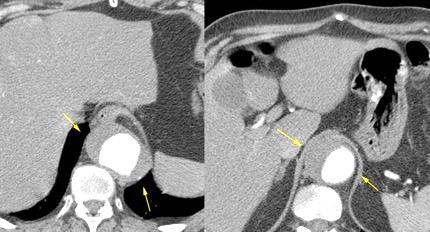

Aneurisma aórtico intracrural

/Restrepo CS et al. The diaphragmatic crura and retrocrural space: normal imaging appearance, variants, and pathologic conditions. Radiographics 2008